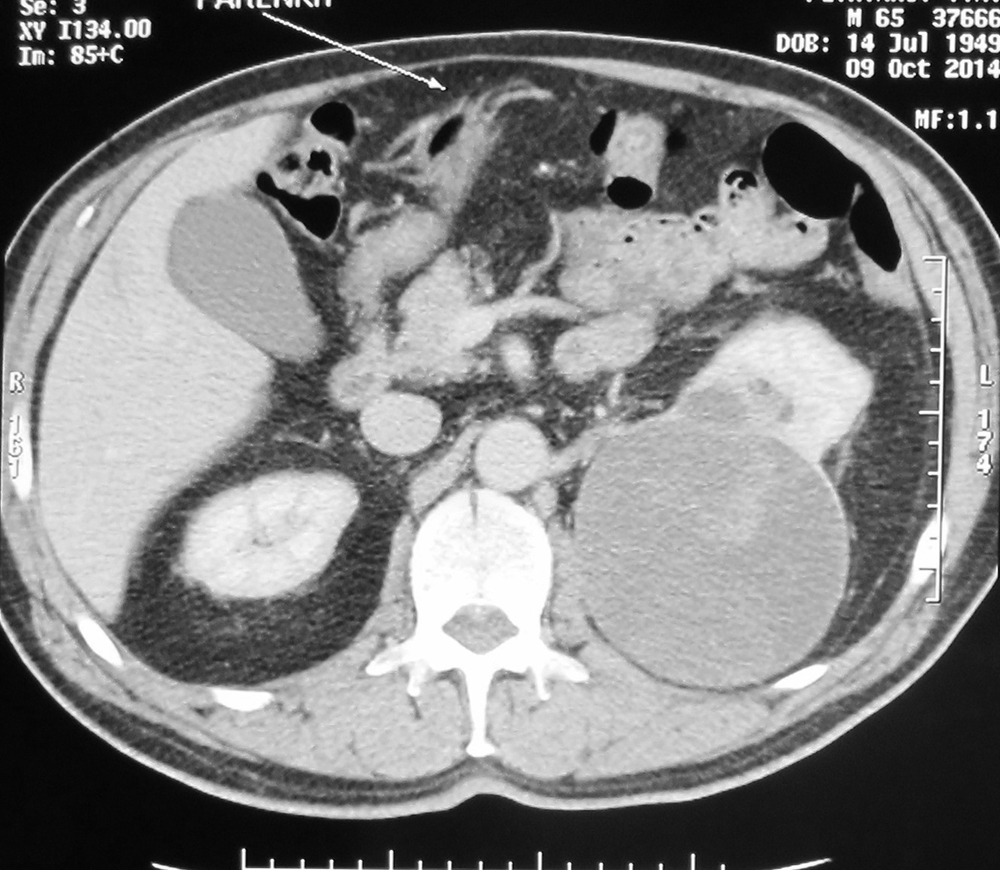

лапароскопичекую нефрэктомию >>>